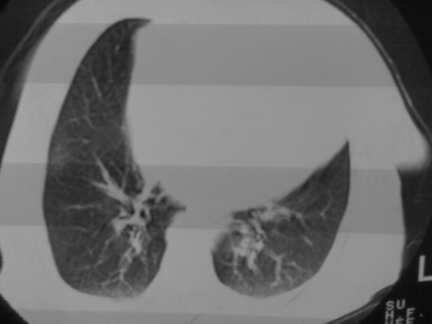

标题: CT13142:女 80 胸闷、气短、1w [打印本页]

标题: CT13142:女 80 胸闷、气短、1w

右肺炎性变,双侧甲状腺肿,胸膜肥厚。

右肺炎性变

气管,支气管软骨钙化。

右肺感染;双侧胸腔少量积液,心影增大,可能与心功不全有关;胸内甲状腺肿。

胸内甲状腺肿;右肺感染;双侧胸腔少量积液。

胸内甲状腺肿;右肺中叶感染;双侧胸腔少量积液;心影增大,考虑有心功能不全。